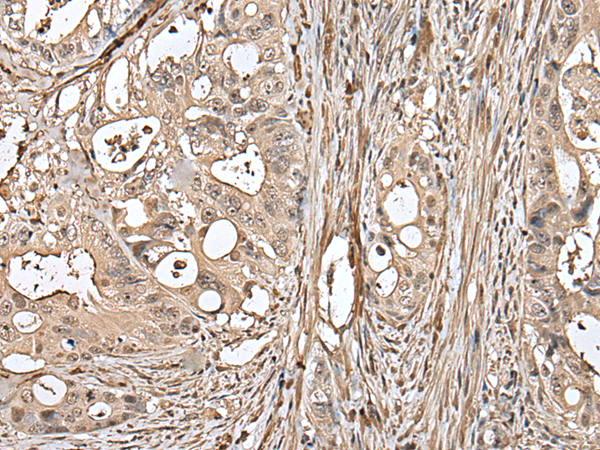

IHC positive control: |

Human colorectal cancer and Human tonsil |